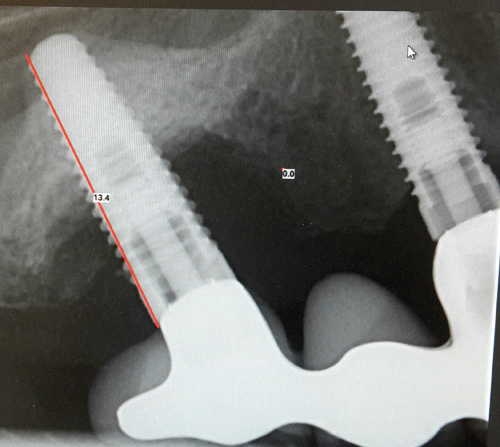

Kasuistikk Kan okklusal overbelastning føre til tap av osseointegrasjon etter vellykket implantatinnsettting? Tapte tenner erstattes i stadig større grad av implantatretinerte protetiske erstatninger. Med flere implantatinnsettinger øker også sannsynligheten for komplikasjoner og feilslag. Peri-implantitt er en biologisk komplikasjon rundt et osseointegrert implantat. I litteraturen er det indikasjoner på at tap av osseointegrasjon er en mer kompleks prosess enn tidligere antatt, der fremmedlegemereaksjon, titanallergi, mikrobevegelse og okklusal overbelastning kan være viktige faktorer i tillegg til plakkindusert infeksjon. Fordi totalbildet av etiologiske faktorer er uklart, mangler klinikeren fortsatt optimale protokoller for behandlingen av peri-implantære komplikasjoner. Les artikkel